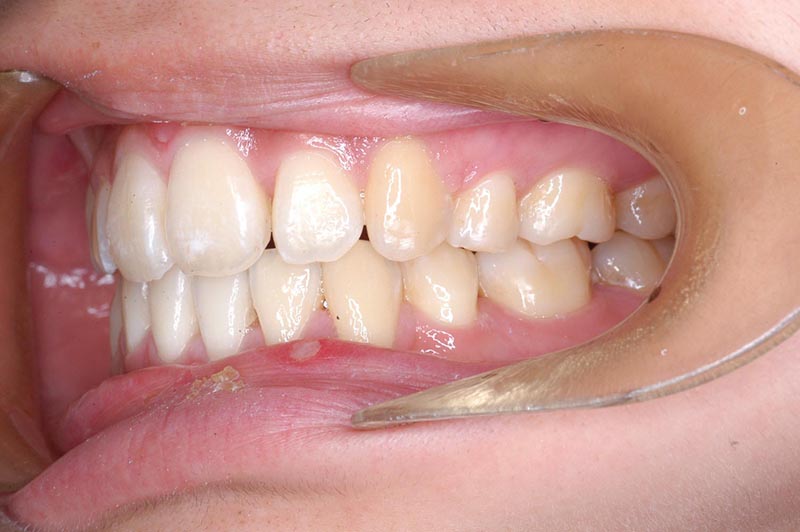

初診時

FP・IOP

主訴 口が閉じづらい 診断名 アングルⅠ級上下顎前突症例

口腔内所見 大臼歯関係はⅠ級。顔面正中に対して上顎正中は一致しており、下顎正中は右側に偏位していた。上下顎前歯は大きく唇側傾斜し、overjetが7.8mmの上突咬合、両突歯列、叢生歯列弓であった。